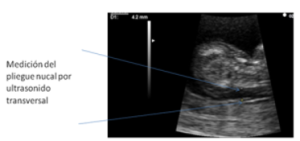

- Medición de la translucencia nucal del feto mediante ecografía y los estudios en sangre de marcadores bioquímicos:

- La edad que ofrece datos más garantizables se encuentra entre la 11ª y la 13ª semana de embarazo.

En el ultrasonido se buscan diversos signos además de la “translucencia nucal”. Por ejemplo: ausencia del hueso nasal, perímetro cefálico, malformaciones de órganos (corazón, tubo digestivo), calcificaciones hepáticas, longitud de femur, etc.